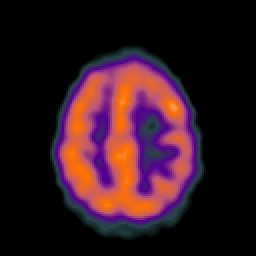

Metastatic bronchogenic carcinoma: Perfusion SPECT -- Slice #16

[Home][Help][Clinical] Slice 16